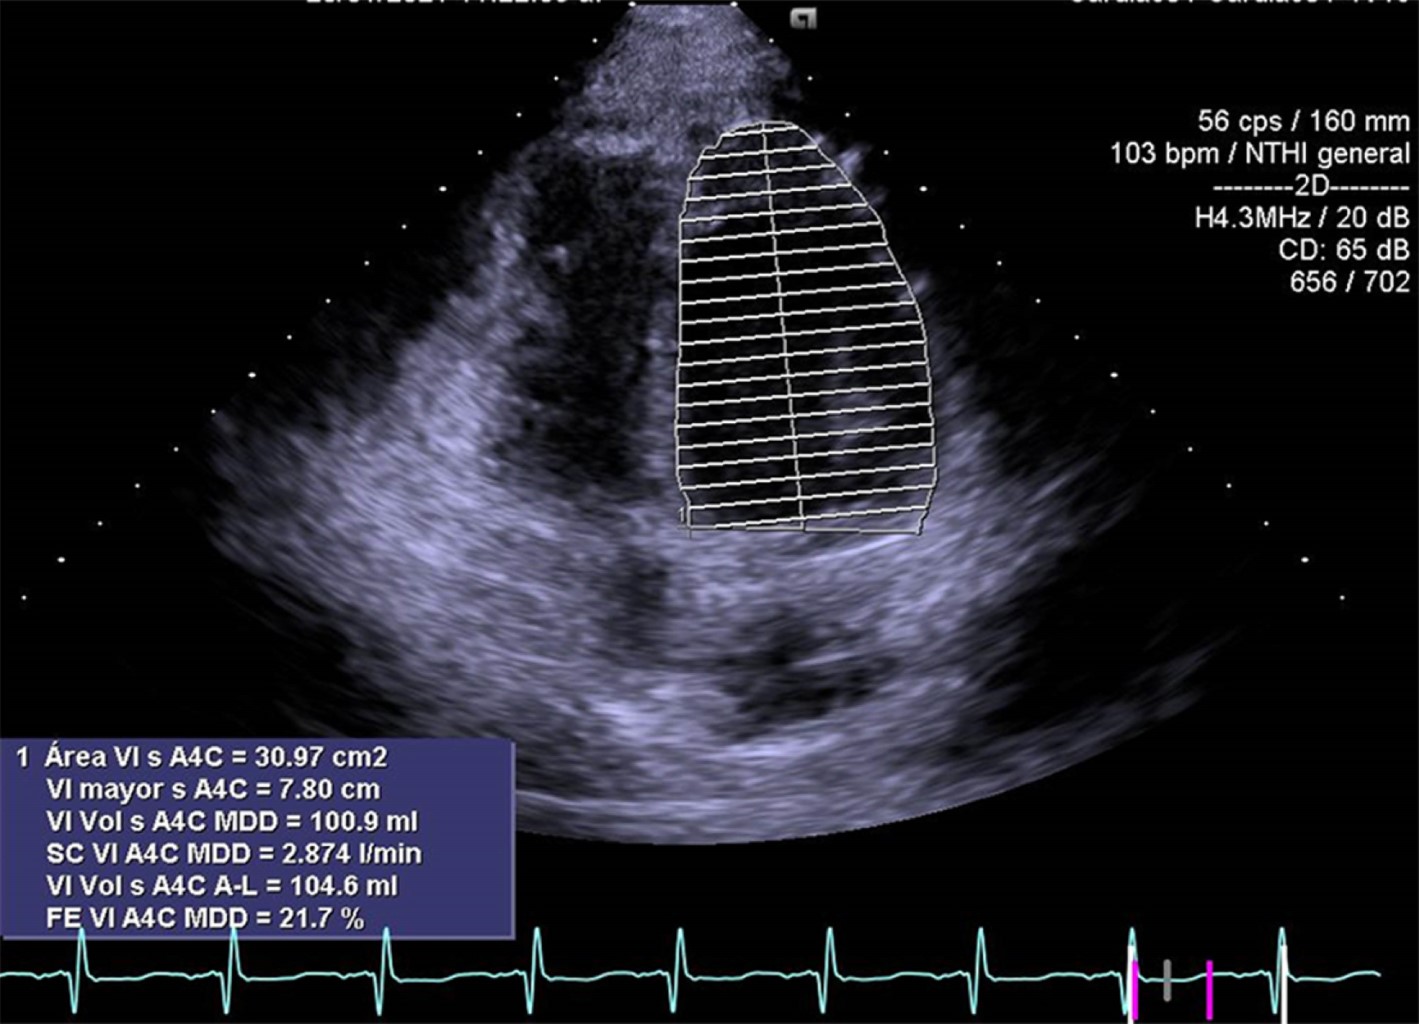

Mujer de 17 años de edad sin antecedentes de importancia, la cual ingresa al área de urgencias trasladada por paramédicos en camilla después de sufrir trauma debido a desaceleración súbita por caída de 10 metros de altura, sufriendo contusión directa y múltiples fracturas en miembros pélvicos, pelvis y cara, por lo que se le realizó colocación de fijadores externos en pelvis y lavado quirúrgico. Ingresó a terapia intensiva con Glasgow de 15 puntos, facies álgica, palidez de piel y tegumentos, con dolor intenso en pelvis escala visual analógica (EVA) 9/10. Con requerimiento de oxígeno suplementario a cinco litros por minuto con disminución de los movimientos de amplexión y amplexación del hemitórax derecho, matidez a la percusión, aumento de las vibraciones vocales y disminución de murmullo vesicular en región basal de hemitórax derecho; signos vitales: presión arterial (TA) 90/50 mmHg, frecuencia cardiaca (FC) 109 latidos por minuto (lpm), frecuencia respiratoria (FR) 16 respiraciones por minuto (rpm), saturación periférica de oxígeno (SpO2) 100%, temperatura 36.6°C, llenado capilar 4 s. Laboratorio: hemoglobina (Hb) 6.8 g/dL, hematocrito (Hct) 19.9%, plaquetas 88,000 × 109/L, tiempo de protrombina (TP) 17.3 s, tiempo parcial de tromboplastina (TPT) 27.5 s, índice internacional normalizado (INR) 1.29, creatina fosfocinasa (CPK) 1,282.52 U/L, isoenzima MB de la creatina cinasa (CPK-MB) 1.2 ng/dL. Se realiza tomografía de abdomen, la cual evidencia hematoma retroperitoneal evolutivo desde plano fascial y perirrenal posterior. La paciente ameritó ventilación mecánica y fue sometida a laparotomía exploradora de urgencia. A su egreso de quirófano y posterior a la reanimación con hemoderivados, continuó con datos de choque con TA 60/40 mmHg, frecuencia cardiaca 105 lpm, llenado capilar 5 s, por lo cual requirió manejo con doble vasopresor: norepinefrina 0.15 μg/kg/min y vasopresina 0.03 UI/h; sin embargo, continua con presión arterial media < 65 mmHg. Se le realiza radiografía de tórax (Figura 1) donde se observa contusión pulmonar en región basal de hemitórax derecho, con corazón en gota. Electrocardiograma (ECG) (Figura 2): ritmo sinusal, frecuencia cardiaca 120 lpm, con aplanamiento de la onda T en la mayoría de las derivaciones excepto en V2, depresión del segmento ST en aVR y ausencia de elevación del segmento ST en V1. Se realizó ecocardiograma transtorácico (ECOTT) (Figuras 3 y 4), en el que se observa movilidad conservada solamente en ápex, condicionando tracción del ventrículo derecho; resto con hipocinesia generalizada, ventrículo derecho dilatado con función sistólica global deprimida con hipocinesia generalizada, fracción de eyección del ventrículo izquierdo (FEVI) 21.7%, puntaje InterTAK de 49 puntos. Requirió manejo con inotrópico dobutamina 3 μg/kg/min con mejoría de presión arterial media y datos de choque. Presentó una evolución favorable, logrando retiro de inotrópico 24 horas después por mejoría con control ecocardiográfico seis días después (Figura 5), con recuperación de FEVI: 64.3%. La paciente requirió fijación de fracturas de huesos de la cara y miembros pélvicos y posteriormente fue trasladada a otra unidad hospitalaria para continuar con tratamiento ortopédico.

Figura 5